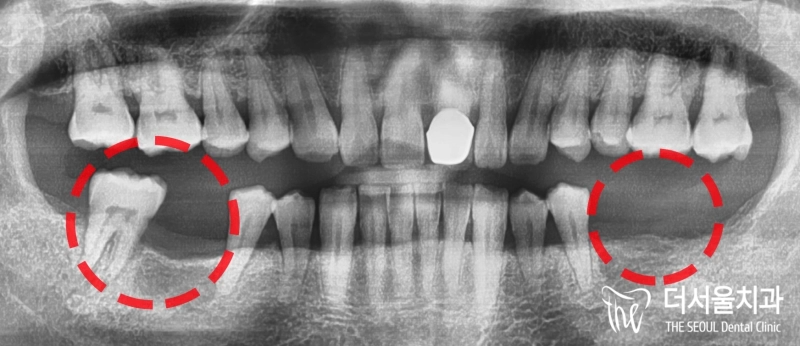

반갑습니다. 잠실 더서울 치과 입니다. 오늘 소개해 드릴 사례는 예전에 찾아오셔서 좌측 아래 어금니 임플란트 식립을 받으셨던 환자분께서 우측